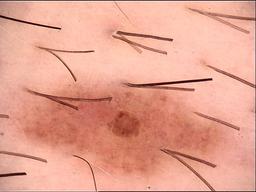

Skin lesion datasets provide essential information for understanding various skin conditions and developing effective diagnostic tools. They aid the artificial intelligence-based early detection of skin cancer, facilitate treatment planning, and contribute to medical education and research. Published large datasets have partially coverage the subclassifications of the skin lesions. This limitation highlights the need for more expansive and varied datasets to reduce false predictions and help improve the failure analysis for skin lesions. This study presents a diverse dataset comprising 12,345 dermatoscopic images with 40 subclasses of skin lesions, collected in Turkiye, which comprises different skin types in the transition zone between Europe and Asia. Each subgroup contains high-resolution images and expert annotations, providing a strong and reliable basis for future research. The detailed analysis of each subgroup provided in this study facilitates targeted research endeavors and enhances the depth of understanding regarding the skin lesions. This dataset distinguishes itself through a diverse structure with its 5 super classes, 15 main classes, 40 subclasses and 12,345 high-resolution dermatoscopic images.